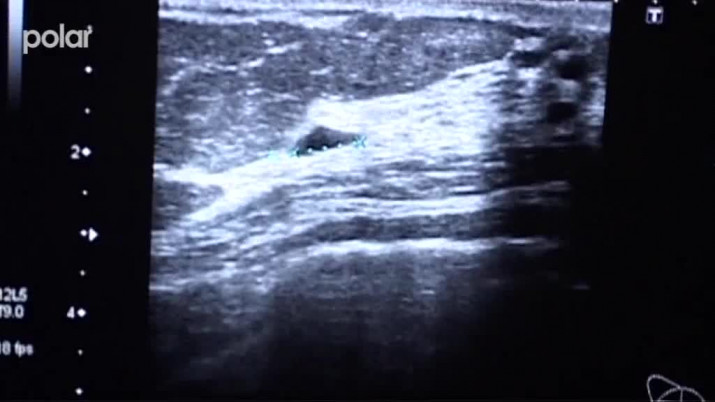

Karvinská hornická nemocnice uvedla do provozu před více než rokem digitální mamograf, který dokáže včas odhalit rakovinu prsu. Vyšetření je důležité zejména pro ženy středního věku, aby se u nich vyloučila, nebo včas diagnostikovala rakovina prsu. Nedávno v nemocnici přibylo i další speciální vyšetření-magnetická rezonance prsu.